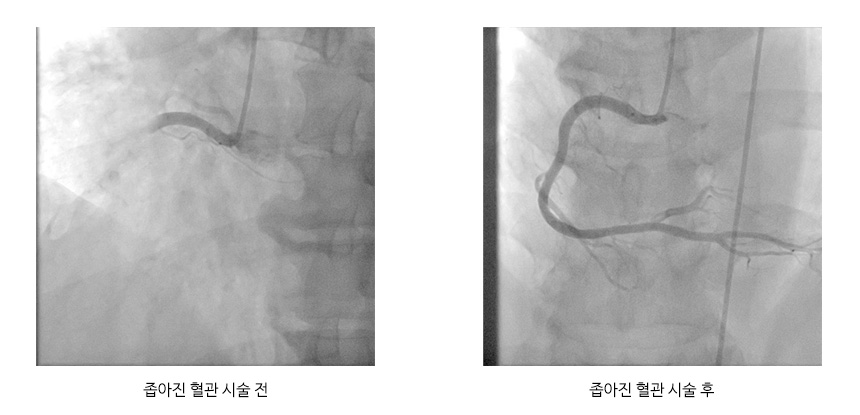

● 진단 심근경색은 심장근육의 괴사로 장기적 합병증이 발생할 가능이 높은 질환으로 병원에 빠르게 도착하여 진단 및 응급조치가 이루어지냐에 따라 생사를 결정하게되며, 피검사, 심장초음파, 심혈관조영술 등 검사를 통하여 진단합니다. ● 치료 심근경색 의심환자로 병원에 도착하면 채혈 및 심전도검사를 통하여 초기진단을 진행하고 심장초음파를 시행하고 약물 및 환자의 상태에 따라 관상동맥조영술을 통한 풍선성형술을 시행합니다. X선 영상에서 동맥이 좁아진 상태를 확인 ![]() |